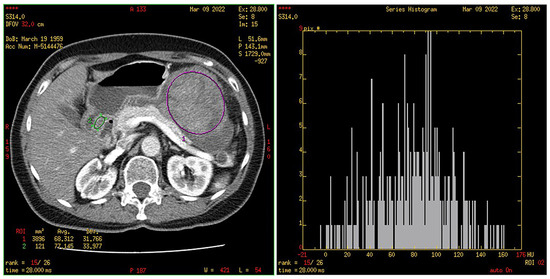

2.4. CT Texture Analysis

3.4. Histogram Parameters in HR and LR Group